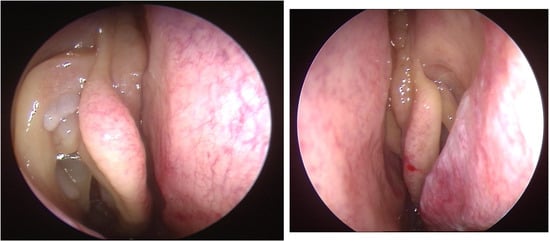

- 0 = no polyps;

- 1 = polyps confined to the middle meatus;

- 2 = multiple polyps occupying the middle meatus;

- 3 = polyps extending beyond the middle meatus;

- 4 = polyps completely obstructing the nasal cavity.

- 1 = small polyps in the middle meatus not reaching the inferior border of the middle meatus;

- 2 = nasal polyps reaching below the lower border of the middle meatus;

- 3 = large polyps reaching the lower border of the inferior turbinate or polyps medial to the middle turbinate;

- 4 = large nasal polyps causing complete obstruction of the inferior nasal cavity.

- Djupesland, P.; Reitsma, S.; Hopkins, C.; Sedaghat, A.; Peters, A.; Fokkens, W.J. Endoscopic grading systems for nasal polyps: Are we comparing apples to oranges? Rhinology 2022, 60, 169–176. [Google Scholar] [CrossRef] [PubMed]

- Gevaert, P.; Gevaert, P.; De Craemer, J.; De Craemer, J.; Bachert, C.; Bachert, C.; Blauwblomme, M.; Blauwblomme, M.; Chaker, A.; Chaker, A.; et al. European Academy of Allergy and Clinical Immunology position paper on endoscopic scoring of nasal polyposis. Allergy 2023, 78, 912–922. [Google Scholar] [CrossRef] [PubMed]